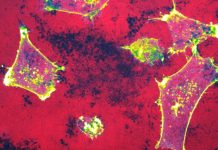

The diversity of patients became even more obvious based on epigenetic profiling of GBM pointing to at least six different entities. Finally, the expression of membrane molecules and receptors, and the existence of different intracellular pathways opened the possibility for targeted therapies. The latter is the key for personalised medicine approaches. The penetration through the blood-brain barrier within the tumour reduces the spectrum of available drugs. One challenge to prove the efficacy of novel targeted therapies within controlled trials is the diversity of the patient population making the design of an appropriate control population almost impossible. This challenge and the need for rapid testing of new compounds have been partially solved with the development of novel clinical trial designs with adaptive randomisation arms and/or external control arms. However, another not yet solved but more important major challenge is the heterogeneity within the tumour and the rapidly changing unpredictable predominance of different tumour sub-clones over time.

The particular tumour micro-environment and tumour-host interaction come on top of these challenges. The connection of the immune system within the brain exists, but has special characteristics. The tumour microenvironment is strongly immune-suppressive, and most GBMs are evaluated as “cold”, without immune cell infiltration. Furthermore, there is a predominance of myeloid cells, partially infiltrated, partially being microglia from the brain itself.

A GBM has even a suppressive influence on systemic immune functioning. Treatments like radiotherapy, chemotherapy and steroids also have negative influences on the systemic immune responses. Again, these negative influences are diverse for each patient. This all means that clinicians have to develop new treatment strategies individualised for each patient at the side of the GBM, at the side of the immune system and at the side of the tumour-host interaction. Treatments should allow adaptations over time, following the individual characteristics of each tumour and patient.